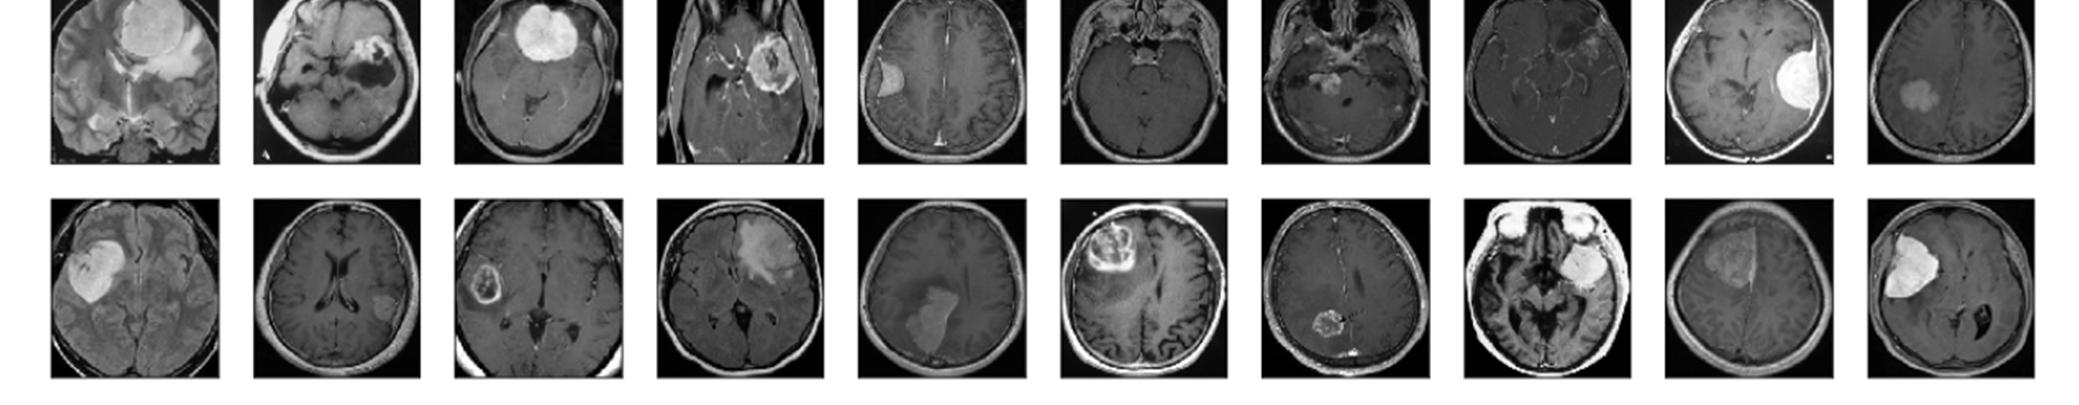

Figure1:Dataset of MRI scans containing no tumors

Figure2: Dataset of MRI scans containing tumors